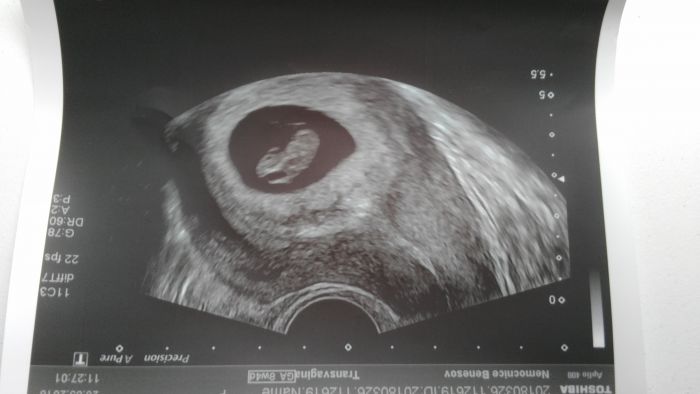

Ahoj holky, mate uz fotky z utz? Ja dnes byla na kontrole a mam radost, protoze i kdyz je mensi, nez by melo byt, tak roste a srdicko tluce :-) jinak podle utz jsem o tyden mene, nez podle ms, tedy 6+5 a prcek ma 7,5mm :-D I tak jsem uz dostala prukazku, coz me prekvapilo, ze tak brzy... Ohledne screeningu se me doktorka ani neptala, jestli chci a rovnou mi rekla, at prijdu 4.5. na testy a donesu si 1000Kc, ze mi to pak pojistovna vrati a 17.5. at prijdeme s manzelem na utz. Pry az tam se zjisti, zda je mimco opravdu v poradku. Uz aby to bylo, takhle mam z kazde kontroly nervy, zda je vse ok

6+5

Utz..ze 7tt..kvuli tomu zda bije srdicko..ted jdeme 12teho..uz se s tatkou tesime...dnesni krece nas oba vydesili..uz nejsem nejmladsi..?